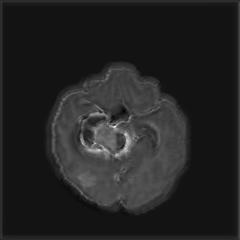

Deep Active Lesion Segmentation

[45]: Lesion segmentation is an important problem in computer-assisted diagnosis that remains challenging due to the prevalence of low contrast, irregular boundaries that are unamenable to shape priors. We introduce Deep Active Lesion Segmentation (DALS), a fully automated segmentation framework that leverages the powerful nonlinear feature extraction abilities of FCNs and the precise boundary delineation abilities of ACMs. Our DALS framework benefits from an improved level-set ACM formulation with a per-pixel-parameterized energy functional and a novel multiscale encoder-decoder CNN that learns an initialization probability map along with parameter maps for the ACM. We evaluate our lesion segmentation model on a new Multiorgan Lesion Segmentation (MLS) dataset that contains images of various organs, including brain, liver, and lung, across different imaging modalities—MR and CT. Our results demonstrate favorable performance compared to competing methods, especially for small training datasets. -